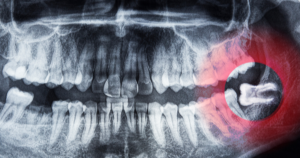

January 3, 2026Wisdom teeth removal is a common dental procedure that many people undergo at some point in their lives. Whether it’s due to overcrowding, impaction, or simply to prevent future dental issues, having your wisdom teeth extracted is often seen as a rite of passage. However, once the procedure is done, the focus shifts to proper aftercare and recovery. One of the most frequently asked questions in this regard is when you can drink after wisdom teeth removal. In this guide, we will address this question and provide you with all the necessary information for a smooth recovery.